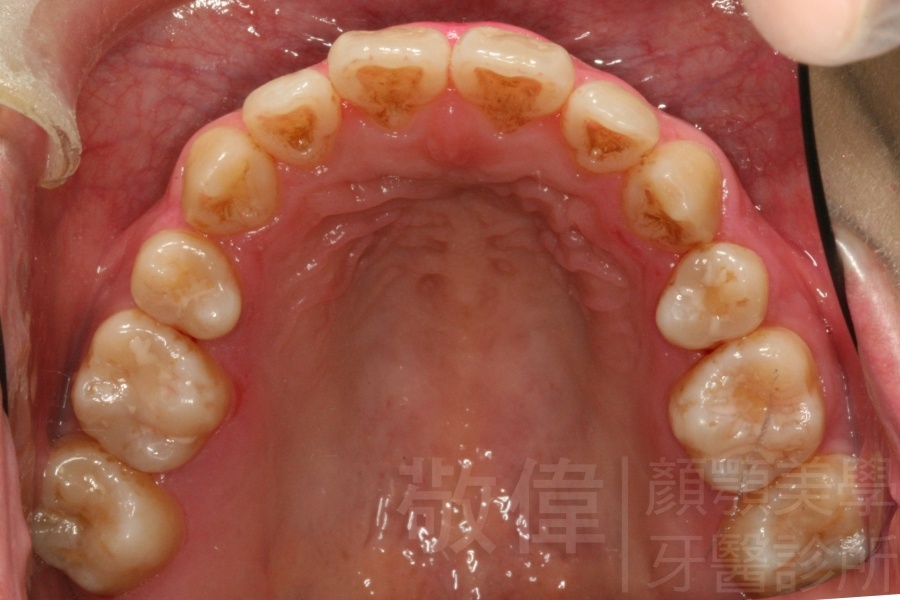

齒顏矯正/戽斗、亂牙、爛牙,變身 免植牙的健牙美女

<個案說明>

變臉矯正,原來戽斗妹跟大歪臉變成自信正妹

經由本院3D數影X光影像儀分析、與3D齒顎顏矯正技術,再配合口腔顎面正顎專科醫師施以正顎手術治療,雙方共同合作,使患者臉部外觀有很好的改善,大歪變小歪,產生了天南地北的大改變,她的人生也整個變得不一樣。